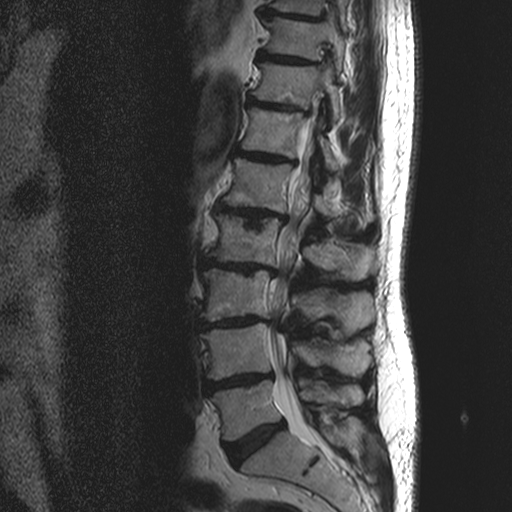

Die MRT-Bilder zeigen einen 27 jähriger Patienten mit plötzlichen Rückenschmerzen mit Ausstrahlung ins linke Bein, über die Wade bis in die äußeren Zehen. Vor allem im Fuss besteht ein Taubheitsgefühl.

In der neurologischen Untersuchung zeigte sich keine Schwäche der Muskulatur, dafür eine Abschwächung des Reflexes an der Ferse und die Taubheit.

Insgesamt kein Grund für eine Operation.

Der Patient wurde konservativ mittels Spritzen, Tabletten und Physiotherapie behandelt.

Das zweite und dritte Bild wurde nach 3 Monaten angefertigt.

Hier zeigt sich der hellgraue Anteil des Bandscheibenvorfalls vollständig resorbiert. Beinschmerzen sind zu diesem Zeitpunkt keine mehr vorhanden. Das Taubheitsgefühl hat sich deutlich verbessert und ist nur noch am kleinen Zeh vorhanden.